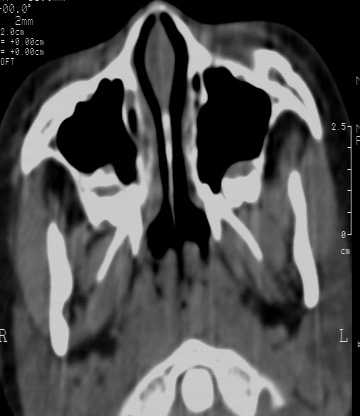

鼻咽腔顶壁及后壁软组织明显肿胀,厚度约2.5cm,鼻咽腔气道轻度狭窄,加之临床病史,支持腺样体肥大。

还可以用鼻咽侧位片测量鼻咽顶部增殖体的厚度和鼻咽腔的宽度,以两者比率来判断儿童增殖体是否肥大。正常时两者比率≤0.60;当比率为0.61~0.70属中度肥大;比率≥0.71属病理性肥大。